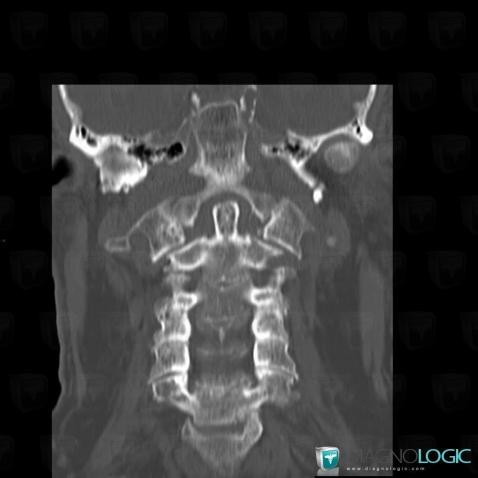

The images below illustrate this case for diagnoses Vertebral fracture, for the modalities (CT)

Vertebral fracture, Vertebral body / Disk, CT

Here is the specific information in the key image above:

- Diagnosis Vertebral fracture, Location(s) Vertebral body / Disk, with gamuts